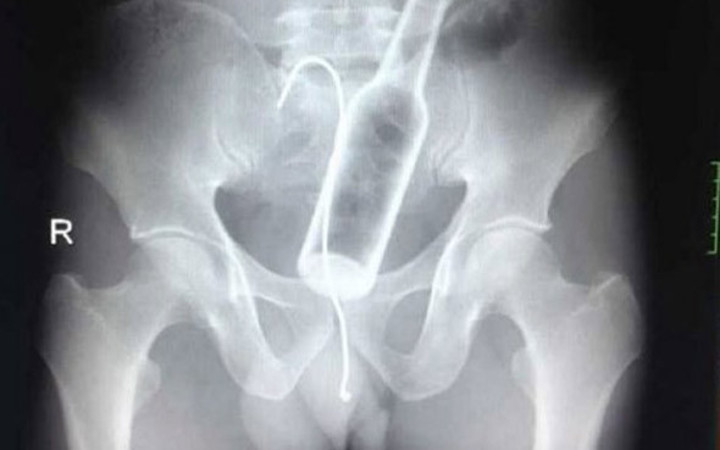

Bir röntgen sonucu neler gösterebilir? Sandığınızdan daha çok şey. Dünyanın dört bir yanından gelen röntgen görüntüleri, görenlerin ağzını açık bırakacak cinsten. Midesinden yasaklı madde çıkan mı dersiniz yoksa ayakkabı mı? Bunlar yapışık ikizlerin röntgeni. Daha ilginçleri ise sizi galerinin devamında bekliyor. İşte birbirinden ilginç ve şaşırtıcı röntgen sonuçları...